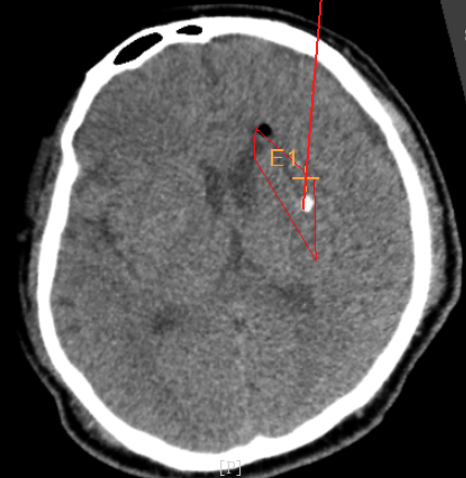

術(shù)前CT:血腫已經(jīng)液化,但仍有占位效應(yīng)

術(shù)前韓帥醫(yī)生使用“睿米”制定手術(shù)規(guī)劃

手術(shù)規(guī)劃在機(jī)器人軟件上制定完成